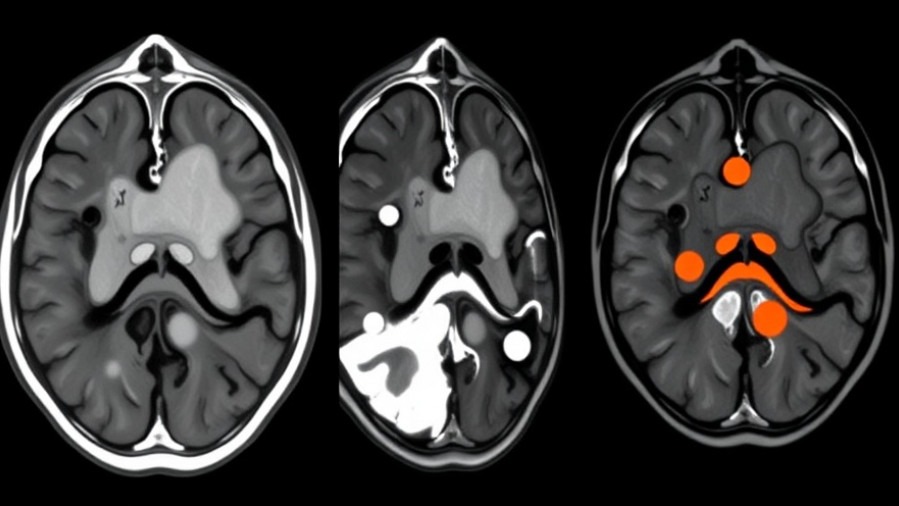

One of the primary advantages of this system is its ability to provide surgeons with a detailed 'malignancy map' of the resection area. This visual representation not only aids in maximizing tumor removal but also minimizes damage to surrounding functional tissues. The integration of real-time data empowers clinicians to make evidence-based decisions at the surgical site, significantly enhancing the precision of tumor removal. For the concierge health practitioners keeping pace with medical innovations, understanding such technology is pivotal as it may directly influence patient outcomes.